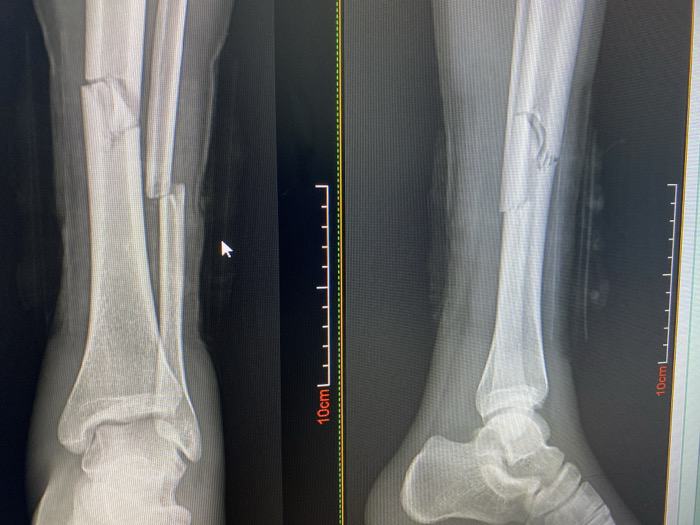

The image displays a photograph of a digital medical monitor showing two distinct X-ray views of a human lower leg. The left X-ray presents an anterior-posterior view, revealing a complete, comminuted fracture of the mid-distal tibia and a co-occurring fracture of the fibula. The right X-ray shows a lateral view of the same leg, confirming the severe fractures, with apparent displacement and multiple bone fragments in the tibia. A white mouse cursor, shaped like an arrow, is visible on the left X-ray image. A vertical measurement scale marked with "10cm" is present on the right edge of the displayed X-ray images. The environment is consistent with a medical diagnostic facility, such as a hospital or clinic, engaged in radiological imaging. The exact location within Abuja, Nigeria, is not discernible from the image's content; however, the scene depicts a standard medical diagnostic setting.